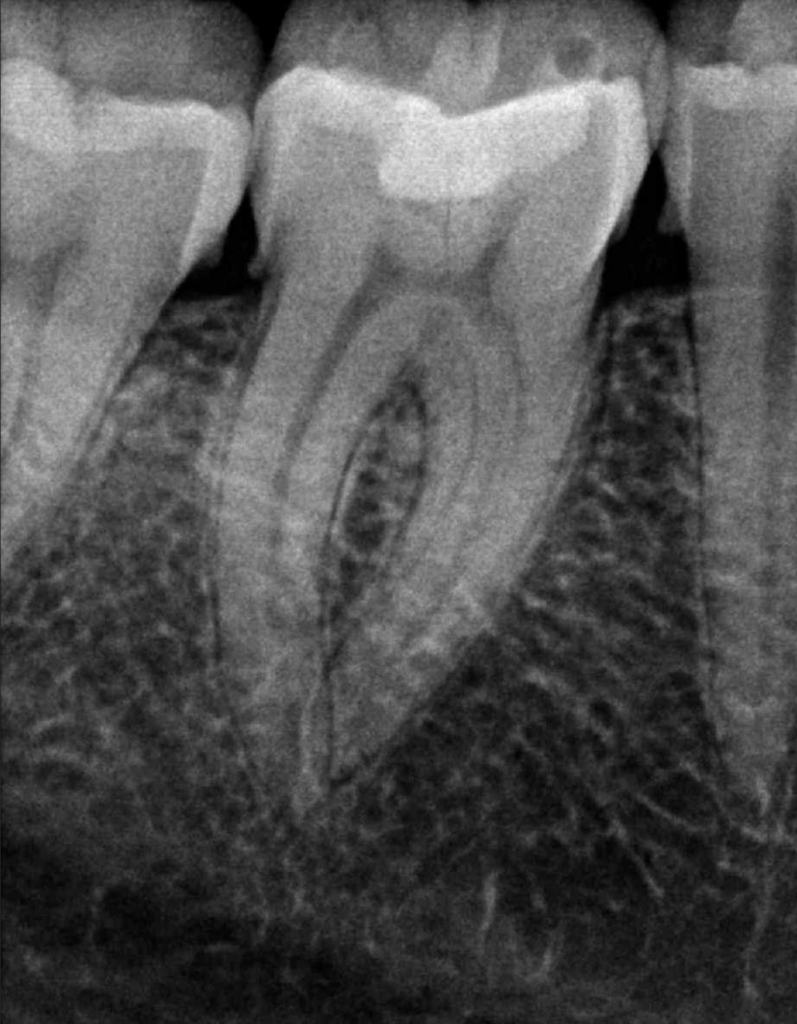

Reabsorción interna